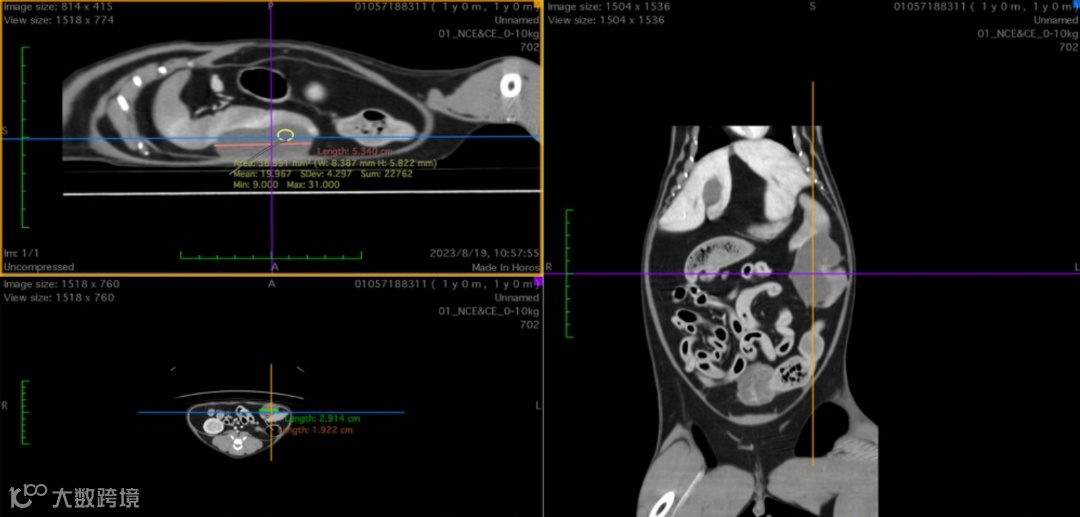

脾尾椭圆形低衰减影像,造影未见增强,大小:5.3×2.9×1.9cm。周围少量不规则软组织衰减影像。疑脾脏血肿,周围微量腹膜腔积液。

左后叶局灶性衰减升高,疑挫伤,未见明显气胸征像。